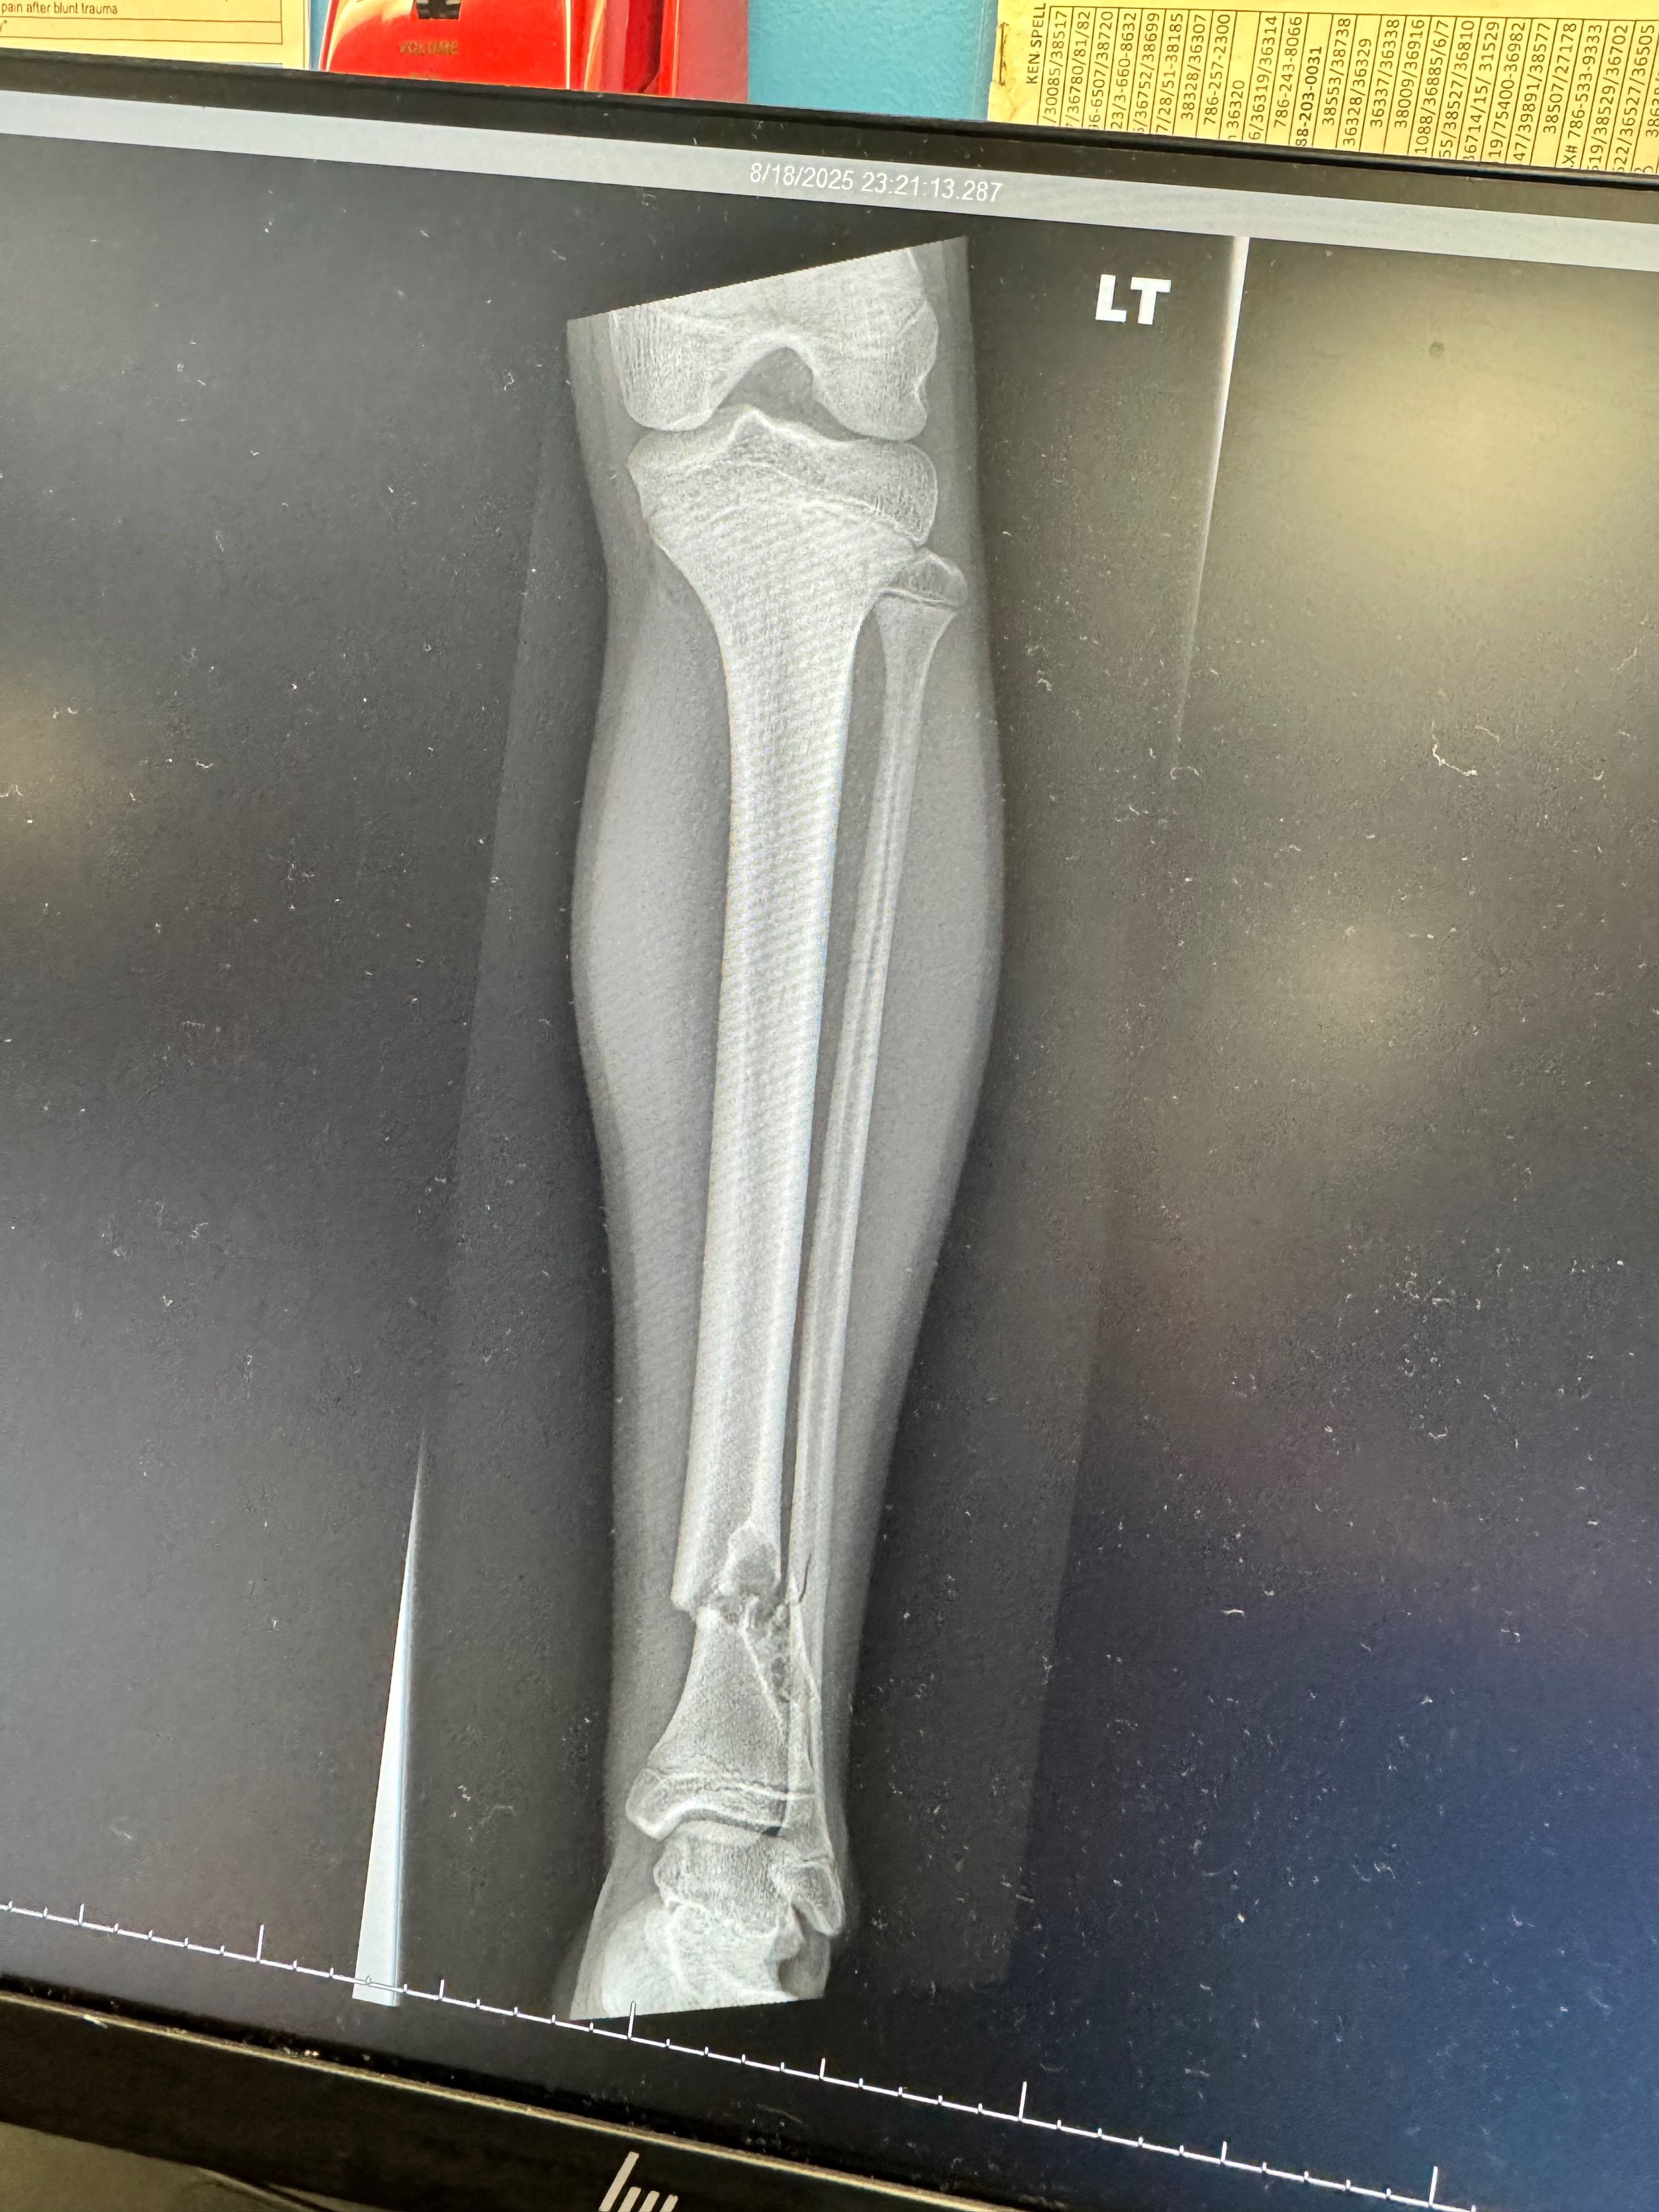

In August of last year, my son Agustín fractured his femur while playing soccer — the sport he loves and a big part of his dreams and goals. What initially seemed like a simple fracture led to the discovery of something more serious: an Aneurysmal Bone Cyst, a bone tumor that has been growing and weakening his bone.

Since then, we have endured months of medical tests, constant monitoring, casts, immobilization, and uncertainty. Recent imaging showed that the tumor has grown, and we are now awaiting a biopsy to confirm that it is completely benign, as doctors strongly believe. With faith, we hope the results will fully rule out cancer so we can proceed with the surgery that is currently scheduled.

En agosto del año pasado, mi hijo Agustín se fracturó el fémur mientras jugaba fútbol, el deporte que ama y que forma parte de sus sueños y metas. Lo que comenzó como una fractura terminó revelando algo más complejo: un Aneurysmal Bone Cyst, un tumor óseo que ha venido creciendo y debilitando su hueso.

Desde entonces, hemos pasado meses de estudios, controles constantes, yesos, inmovilizaciones y mucha incertidumbre. Recientemente, los exámenes mostraron que el tumor ha crecido, y ahora estamos esperando una biopsia para confirmar que sea completamente benigno, como los médicos sospechan. Con fe, esperamos que el resultado descarte cualquier posibilidad de cáncer y que podamos proceder con la cirugía ya programada.